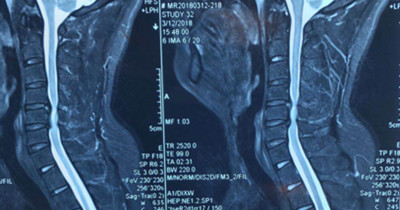

患者王先生,34歲,兩個月來自覺行走時雙下肢無力,伴踩棉花感,休息后癥狀無明顯緩解,雙手指麻木,呈加重趨勢。一月前就診于骨一科。確診為頸椎?。顾栊停?。病變部位位于頸5-6平面。

圖片一:

因患者年齡較輕,雙下肢無力癥狀明顯,病變區(qū)脊髓信號改變,保守治療病情會繼續(xù)發(fā)展,后期脊髓神經(jīng)變性,壓迫癥狀加重,嚴(yán)重影響肢體功能,必須盡早手術(shù)。骨一科主任楊志奎帶領(lǐng)曹熙、田濤、張凱迪醫(yī)師為其實(shí)施了頸椎前路頸5椎體次全切、椎管減壓植骨融合內(nèi)固定術(shù)。手術(shù)歷時3小時順利完成。術(shù)后第二天,患者雙手指麻木癥狀明顯緩解,四肢關(guān)節(jié)活動均正常。第三天配帶頸托保護(hù)下床活動鍛煉,雙下肢無力癥狀明顯減輕。患者現(xiàn)已康復(fù)出院。